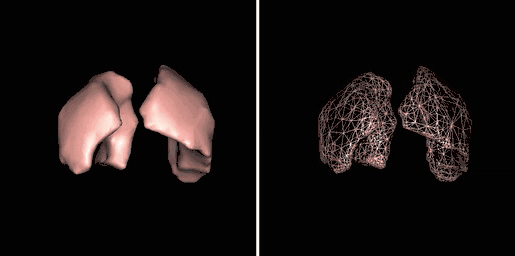

Surface rendering is also referred to as Shaded Surface Display (SSD) and involves generating surfaces from regions with similar voxel values in the 3D data as illustrated by the SPECT lung-perfusion scan shown in the left panel below:

3D surface rendering: shaded surface and wireframe display.

The process involves the display of surfaces which might potentially exist within the 3D voxel data on the basis that the edges of objects can be expected to have similar voxel values. One approach is to use a grey-level thresholding technique where voxels are extracted once a threshold value is encountered in the line of the projection – see the following diagram. Triangles are then used to tesselate the extracted voxels, as shown in the right panel of the figure above – and the triangles are filled using a constant value with shading applied on the basis of simulating the effects of a fixed virtual light source – as shown in the left panel above.

Illustration of surface rendering.